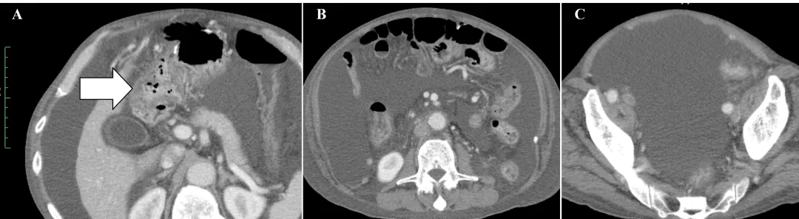

案例2:难治性宫颈癌转移灶消失,免疫功能恢复

小细胞未分化宫颈癌进展快、易耐药,预后极差。《Cureus》报道了一则突破性案例:一位 50 多岁的患者术后出现肝、淋巴结多处转移,化疗失败后,采用 WT1-DC 疫苗联合放疗: 1、第 67 天(注射第 5 剂疫苗后),CT 显示肝转移灶完全消失; 2、免疫指标(中性粒细胞 / 淋巴细胞比值等)恢复正常,原本因化疗受损的免疫功能显著改善。 案例3:胰腺癌患者中位生存期突破3年,7人成功手术 胰腺导管腺癌被称为 “癌王”,对放化疗天然耐药。《癌症免疫治疗杂志》的一项研究带来了新希望:10 例不可切除的胰腺导管腺癌患者(6 例 III 期局部晚期、3 例 IV 期转移性、1 例术后复发)采用 WT1-DC 疫苗联合化疗后: 1、所有患者肿瘤负荷下降,7人达到部分缓解,3人长期稳定; 2、9例患者中位无进展生存期 2.23 年,中位总生存期更是突破 3.52 年,远超传统治疗的预期。 3、 7 例成功接受了转化手术,其中 6 例实现 R0 切除(肿瘤完全切除,无残留),1 例为 R1 切除(镜下有残留)。 案例4:晚期十二指肠癌 4.3 年无进展,恶性腹水消失 十二指肠癌占胃肠道癌症的 0.3%-0.5%,虽发病率低但侵袭性强,易快速扩散,根治性手术是唯一可能治愈的手段,但晚期患者往往失去手术机会,且针对恶性腹水缺乏有效治疗方案。 《Cureus》曾报道一则案例:一位 72 岁的晚期十二指肠癌患者,腹膜播散伴恶性腹水,化疗失败后接受 WT1/MUC1-DC 疫苗联合细胞疗法: 1、第 8 次治疗后,恶性腹水消失,腹胀、水肿等症状消退; 2、原发病灶和转移淋巴结缩小,截至报道时,肿瘤 52 个月未进展,患者未出现严重副作用,且能正常活动。 锐赛EP-DC(医迪泰)是一种通用型的DC细胞疫苗,可靶向激活免疫系统对22种常见肿瘤抗原的免疫反应。产生强大免疫应答(CD4+/CD8+)识别所有肿瘤抗原,并覆盖广泛HLA类型。 当向患者给药时,医迪泰诱导的免疫应答有可能识别及破坏体内的癌细胞并向免疫系统持续提供支持和记忆,以便其能够持续靶向及预防癌症复发的可能。 2025年初,顶尖期刊Small Science(IF 12.7)发表了星空娱乐首席科学家范小勇教授与复旦大学附属上海市公共卫生临床中心研究组、南方科技大学附属深圳市第三人民医院/国家感染性疾病临床医学研究中心研究组的合作研究,题为“Dendritic Cell Vaccine Harboring Inactivated Mycobacteria Induces Immune Protection Against Tuberculosis in Murine Models and is Well Tolerated in Humans”。 本研究在上海市重大传染病和生物安全研究院官网的报道 该项临床研究使用了锐赛自主知识产权的新一代EP-DC疫苗技术。此前,这一创新技术已在多项抗肿瘤、抗HPV病毒治疗的临床研究中被证明有效。本次研究是EP-DC技术在结核病临床研究的重磅亮相。 星空娱乐负责制备DC 范小勇教授团队的突破性研究,首次证实DC细胞应用有望成为预防和治疗结核病的新策略。同时也揭示了新一代EP-DC疫苗技术可以在感染疾病的全病程治疗中发挥重大作用。 随着论文的发表,说明锐赛新一代EP-DC疫苗技术的应用场景已从肿瘤治疗的最后防线,扩展至疾病预防、病原微生物清除、病理进展逆转、疾病辅助治疗和术后防复发的全流程。